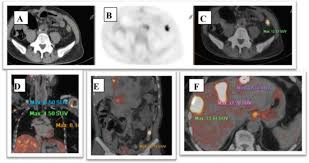

Can Cat Scan Find Colon Cancer / Molecular Imaging Using Positron Emission Tomography In Colorectal Cancer Michael Lin Discovery Medicine / Colonoscopy is best known for its use as a screening tool for the early detection of colorectal cancer.. Ct scans can produce false negatives and false positives. In addition to intraluminal structures like polyps, a ct scan of the colon can also detect extraluminal abnormalities. Dad also had a biopsy done a fortnight ago. Identifying these lesions on ct scan performed for nonspecific symptoms can help identify interval crc and improve patient outcome. Binderow continues, ct is very good for solid organ disease — liver, spleen, kidneys.

Ct Scan Uses Side Effects Procedure Results from www.verywellhealth.com Ct scan of the colon has the advantage of being less invasive than colonoscopy. Ct scans can produce false negatives and false positives. Estimates that any one person's risk of cancer from a ct scan is much lower than their risk of getting cancer naturally. Colorectal cancer is the 3rd most common type of cancer and the 3rd leading cause of cancer death in the united states. It can show metastatic colon cancer that has spread to the liver. If your ct was clear you can at the very least rule out a later stage of colon cancer. Ct colonography is a computed tomography (ct) examination to look at the large bowel (colon). Just a couple corrections to the other answers.

Ct scans overstaged and understaged ct in 23.7% and 48.3% and cn in 28.7% and 53.0% of cases. The endoscopy has an additional benefit of allowing small polyps to be biopsied or removed. The scan is painless and takes about 10 to 30 minutes. None of my ct scans report about the colon tumour. I performed an scope examination of her esophagus and confronted a huge cancer occupying the lower portion of her esophagus. Ct colonography (also known as virtual colonoscopy) can be used to screen for both large colorectal polyps and colorectal tumors.ct colonography uses the same dose of radiation that is used in standard ct of the abdomen and pelvis. It is a method of diagnosing bowel cancer when it is still at an early stage. To try to detect recurrences as early as possible, people who have finished colorectal cancer treatment regularly return to their doctors for imaging tests (like ct or mri scans) and a blood test to detect cea, a substance that can indicate if cancer is growing. Early colorectal cancer can be subtle on ct scans showing only mild wall thickening, small polyps, or subtle lymph nodes in atypical draining location. Pet scans are not routinely done in people diagnosed with colorectal cancer. Binderow continues, ct is very good for solid organ disease — liver, spleen, kidneys. A ct scan can be wrong: Posted 2 years ago, 5 users are following.

Dad also had a biopsy done a fortnight ago. Just a couple corrections to the other answers. The resolution of the newest ct scanners is a couple millimeters ,not a centimeter. If your ct was clear you can at the very least rule out a later stage of colon cancer. Are you preparing to have this procedure soon? Ct scans and mris are used more often. I expected a benign explanation for her swallowing issue. Ct scans overstaged and understaged ct in 23.7% and 48.3% and cn in 28.7% and 53.0% of cases. Positron emission tomography (pet) scan for a pet scan, a slightly radioactive form of sugar (known as fdg) is injected into the blood and collects mainly in cancer cells. Colorectal cancer is the 3rd most common type of cancer and the 3rd leading cause of cancer death in the united states. I performed an scope examination of her esophagus and confronted a huge cancer occupying the lower portion of her esophagus. Ct scans can be misread or misinterpreted. Unlike screening exams, which primarily find cancer in the colon, these staging exams help your doctor check the rest of your body for cancerous cells that may have metastasized, or spread, outside of the colon.

Dad also had a biopsy done a fortnight ago. A female patient came to see me with some difficulty swallowing, a very routine issue for a gastroenterologist. None of my ct scans report about the colon tumour. Pet scans are not routinely done in people diagnosed with colorectal cancer. I wonder why it doesn't show up. A ct scan can be wrong: Colorectal cancer is the 3rd most common type of cancer and the 3rd leading cause of cancer death in the united states. Ct scans overstaged and understaged ct in 23.7% and 48.3% and cn in 28.7% and 53.0% of cases. Unlike screening exams, which primarily find cancer in the colon, these staging exams help your doctor check the rest of your body for cancerous cells that may have metastasized, or spread, outside of the colon. Early colorectal cancer can be subtle on ct scans showing only mild wall thickening, small polyps, or subtle lymph nodes in atypical draining location. Imaging tests usually can't tell if a change has been caused by cancer. A ct is not the best test to diagnose colon cancer. Does/or did your colon, rectal tumour show in the ct scan, and did the radiologist report on it.